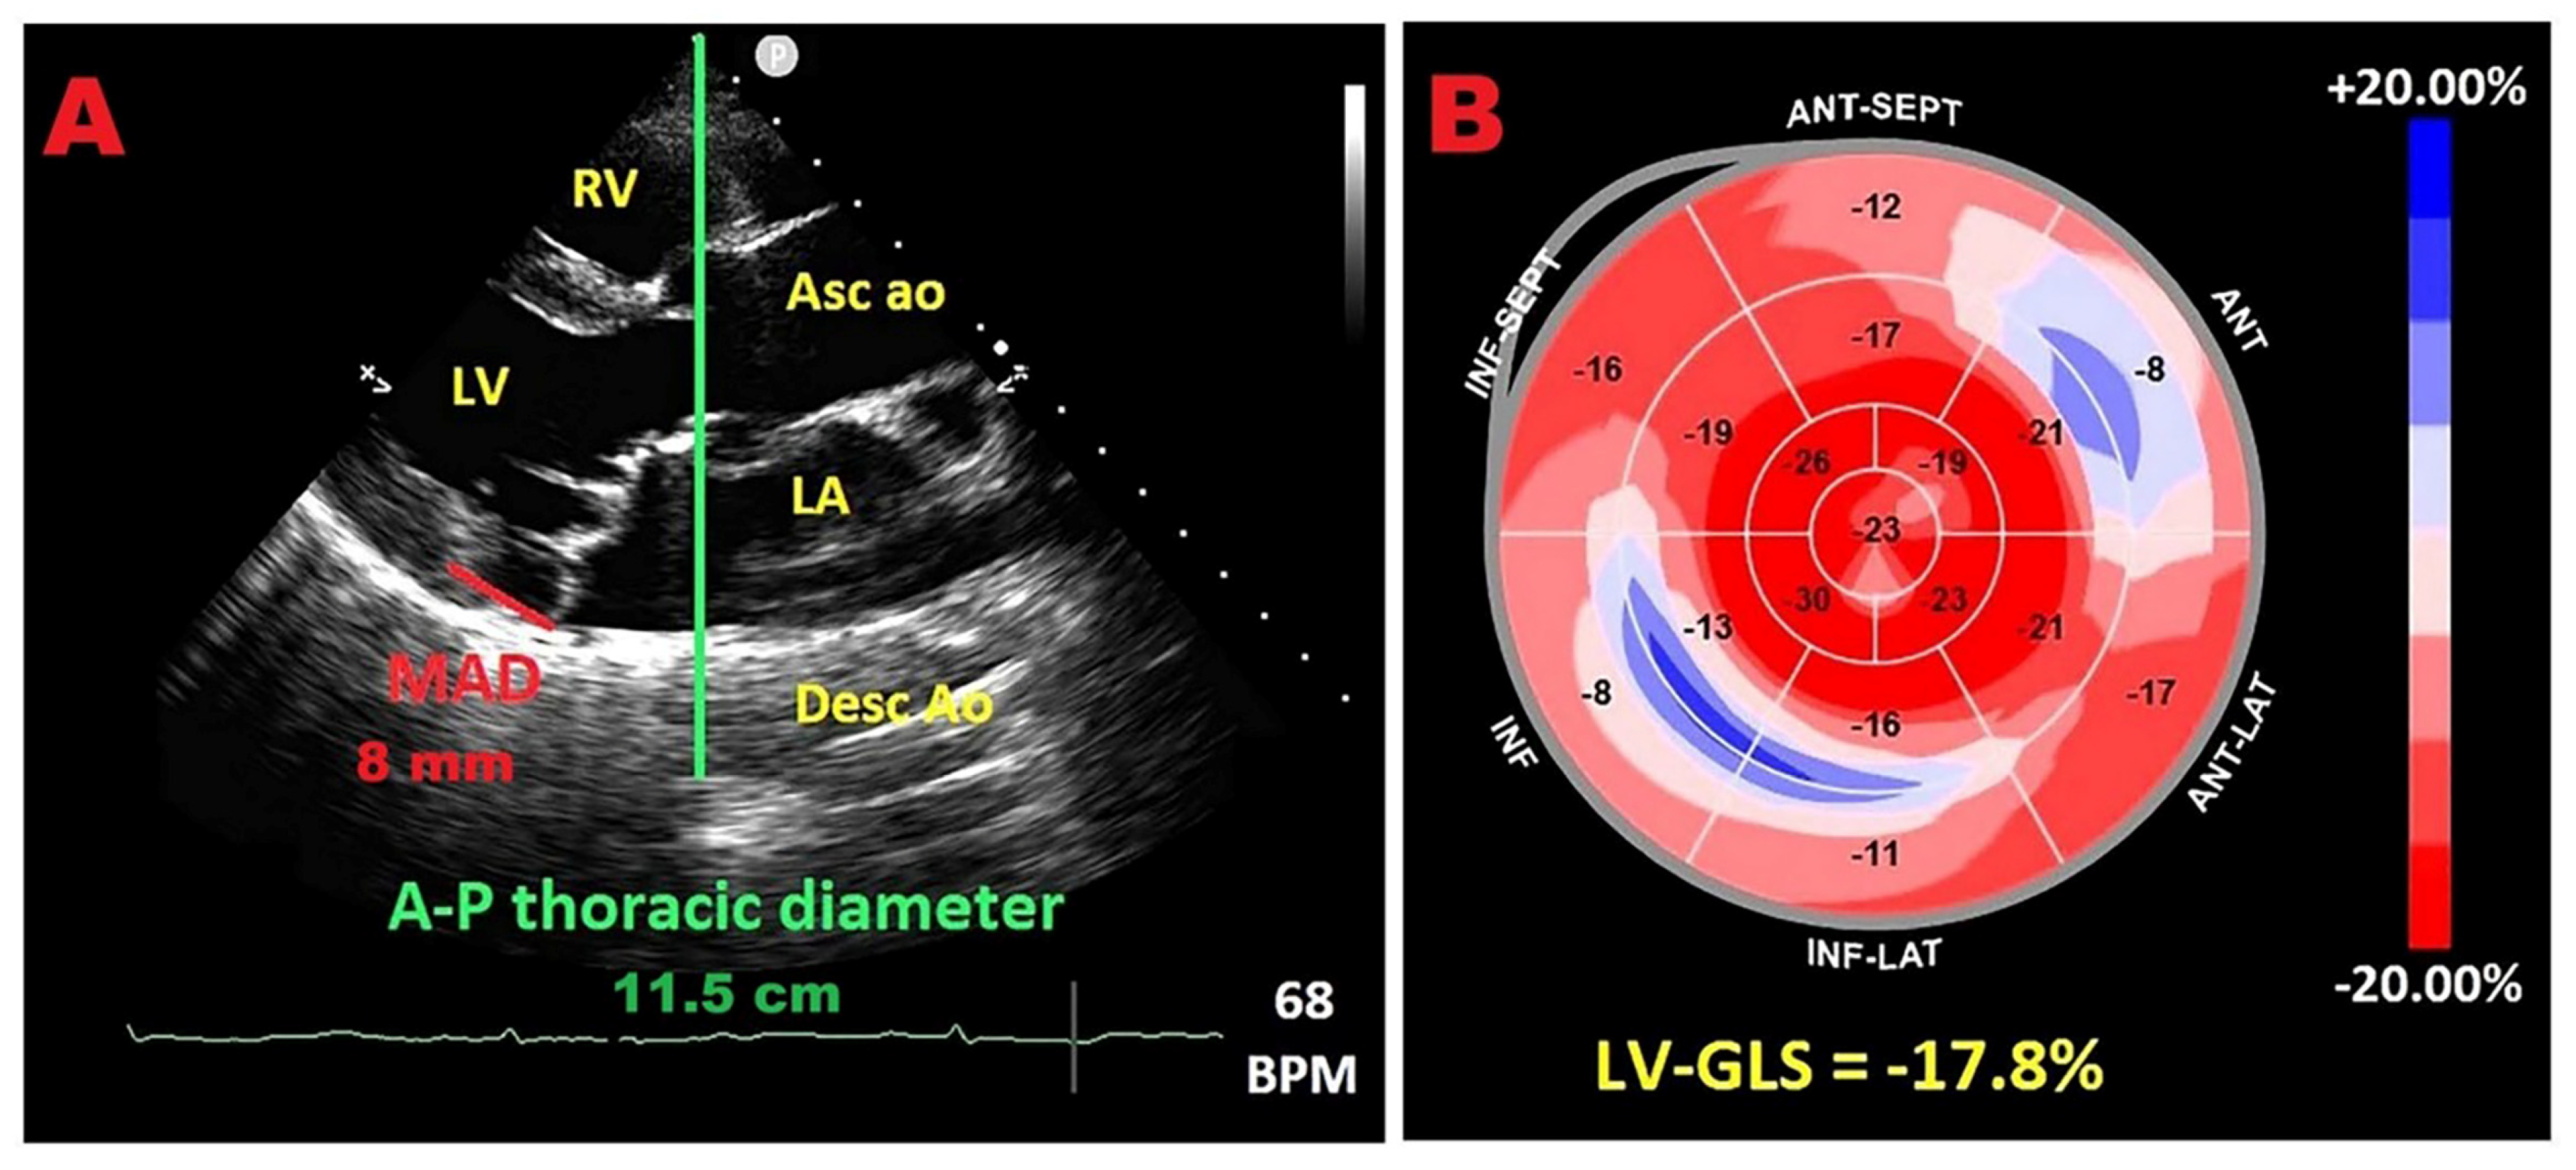

9.2. Relationship Between Chest Wall Conformation and MAD Distance in PMR with MVP

9.3. Potential Link Between Concave Chest Morphology and a “Benign MAD Phenotype”

9.4. Influence of Chest Wall Conformation on ESE Results